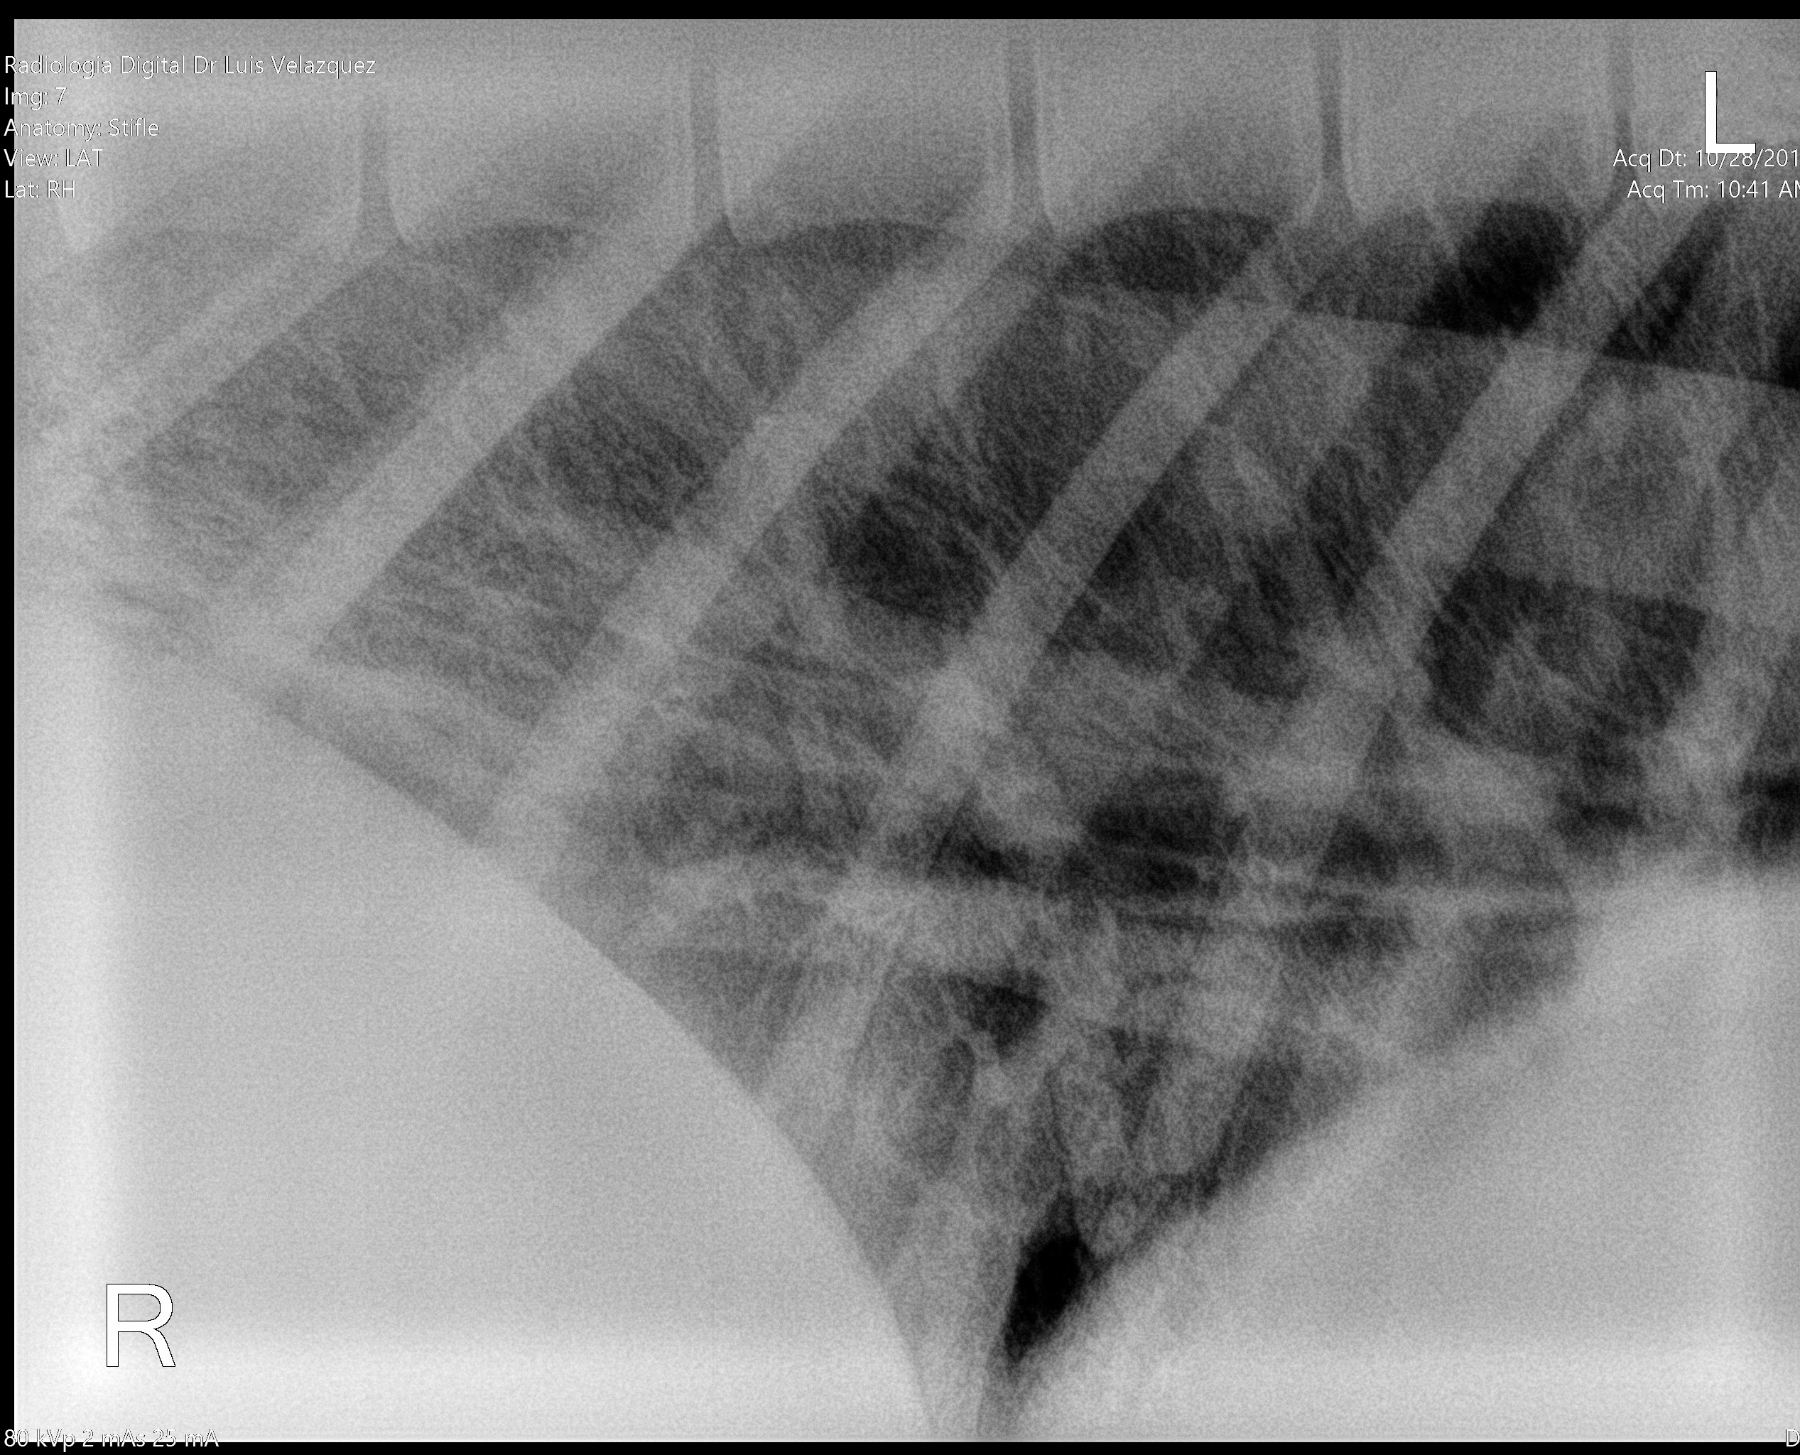

Cambios Térmicos en las Extremidades de Caballos,

Asociados a Golpes y su Evaluación por Termografía.

Los caballos de salto, en competencia, pueden derribar obstáculos y lastimarse. Si se golpean, no siempre claudican. Considerando al calor como un signo de inflamación, se evaluaron los cambios térmicos de 6 áreas de las extremidades torácicas y pelvianas de 23 caballos de salto en nivel de competencia de 1.05 a 1.60 m de altura, por medio de termografía durante 4 días de competencia (N=2208 áreas).